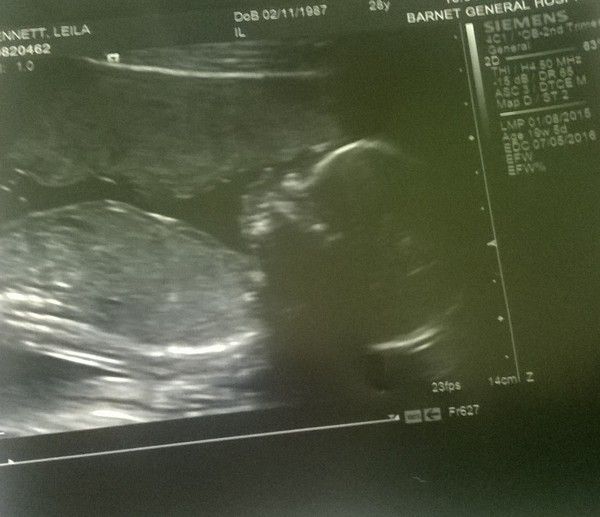

Scan all clear and very active baby shaped thing in there, lol!! So relieved and still shaking!

All good here too, just about 12 week wriggling baby Smile. Nice lady in Epau offered me a scan at 14 weeks, so why not! Have proper 12 week scan on Tuesday.

Congratulations on the positive 12 week scans cotton and eastend. Let the count down to your 20 week scans begin!

Where has all the time gone?! So many of us are now on may leave, feels like such a long time away for me! We had our scan last week and saw a lovely jumpy baby who even gave us a wave! I braved using my Doppler too and found the heartbeat really quickly.

carrie&tinks nice to hear from you! Great news about the scan! Not so great about the bleeds, but glad all is now well! Congrats on dd, we found out yesterday at our 20 week scan we're having a 'samuel' Xmas Wink